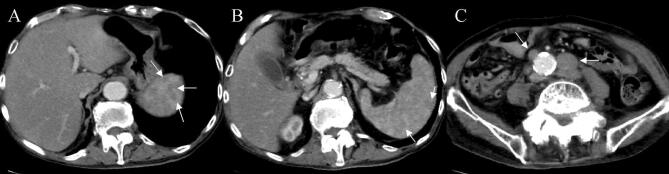

Fig. 1.

A CT examination revealed no distinct nodules or masses in the liver, but mild splenomegaly, multiple hypodense splenic lesions (a, b), and para-aortic lymph-node swelling (c)

The second implication of our case is that CT revealed no distinct nodules or masses in the liver but multiple hypodense lesions in the spleen. It has been reported that radiographic studies are typically notable for the absence of large mass lesions and reveal only a nodular liver in some cases that may be described as pseudocirrhosis, given that fulminant presentations are commonly associated with diffuse intra-sinusoidal infiltration [1]. Additionally, hepatosplenomegaly and lymphadenopathy may also be seen on CT [1, 5], and the CT findings are shown to be similar in the ten cases reported to date (Table 1). While two cases of multiple hypodense splenic lesions have been reported in ALF associated with malignant lymphoma, no pathological examination has been performed in these cases [10, 16]. Of note, a pathological examination in our case clearly revealed that the multiple hypodense splenic lesions detected were metastatic lesions of the primary malignant lymphoma. This finding, including the presence of lymphadenopathy on CT, may prove helpful in predicting the presence of ALF associated with malignant lymphoma.

In conclusion, diffuse large B-cell lymphoma presented as ALF. ALF associated with malignant lymphoma should be suspected in patients with ALF in the absence of distinct nodules or masses in the liver but in the presence of multiple hypodense lesions in the spleen or lymphadenopathy on CT.